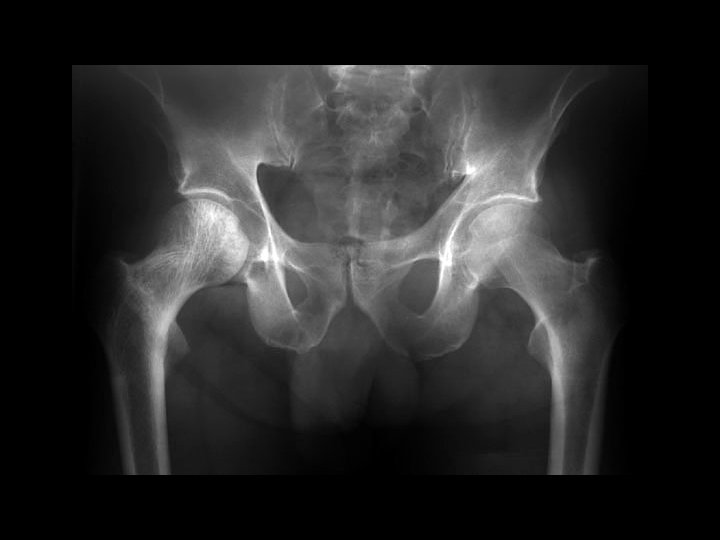

Ankylosing Spondylitis • Findings: – fused SI joints – right hip erosions – lumbar syndesmophytes • Sero-negative chronic inflammatory disease • Starts in the low back and progesses upward • ddx (sacroilitis) – bilateral • ank spond • IBD – unilateral • Reiter’s • psoriasis